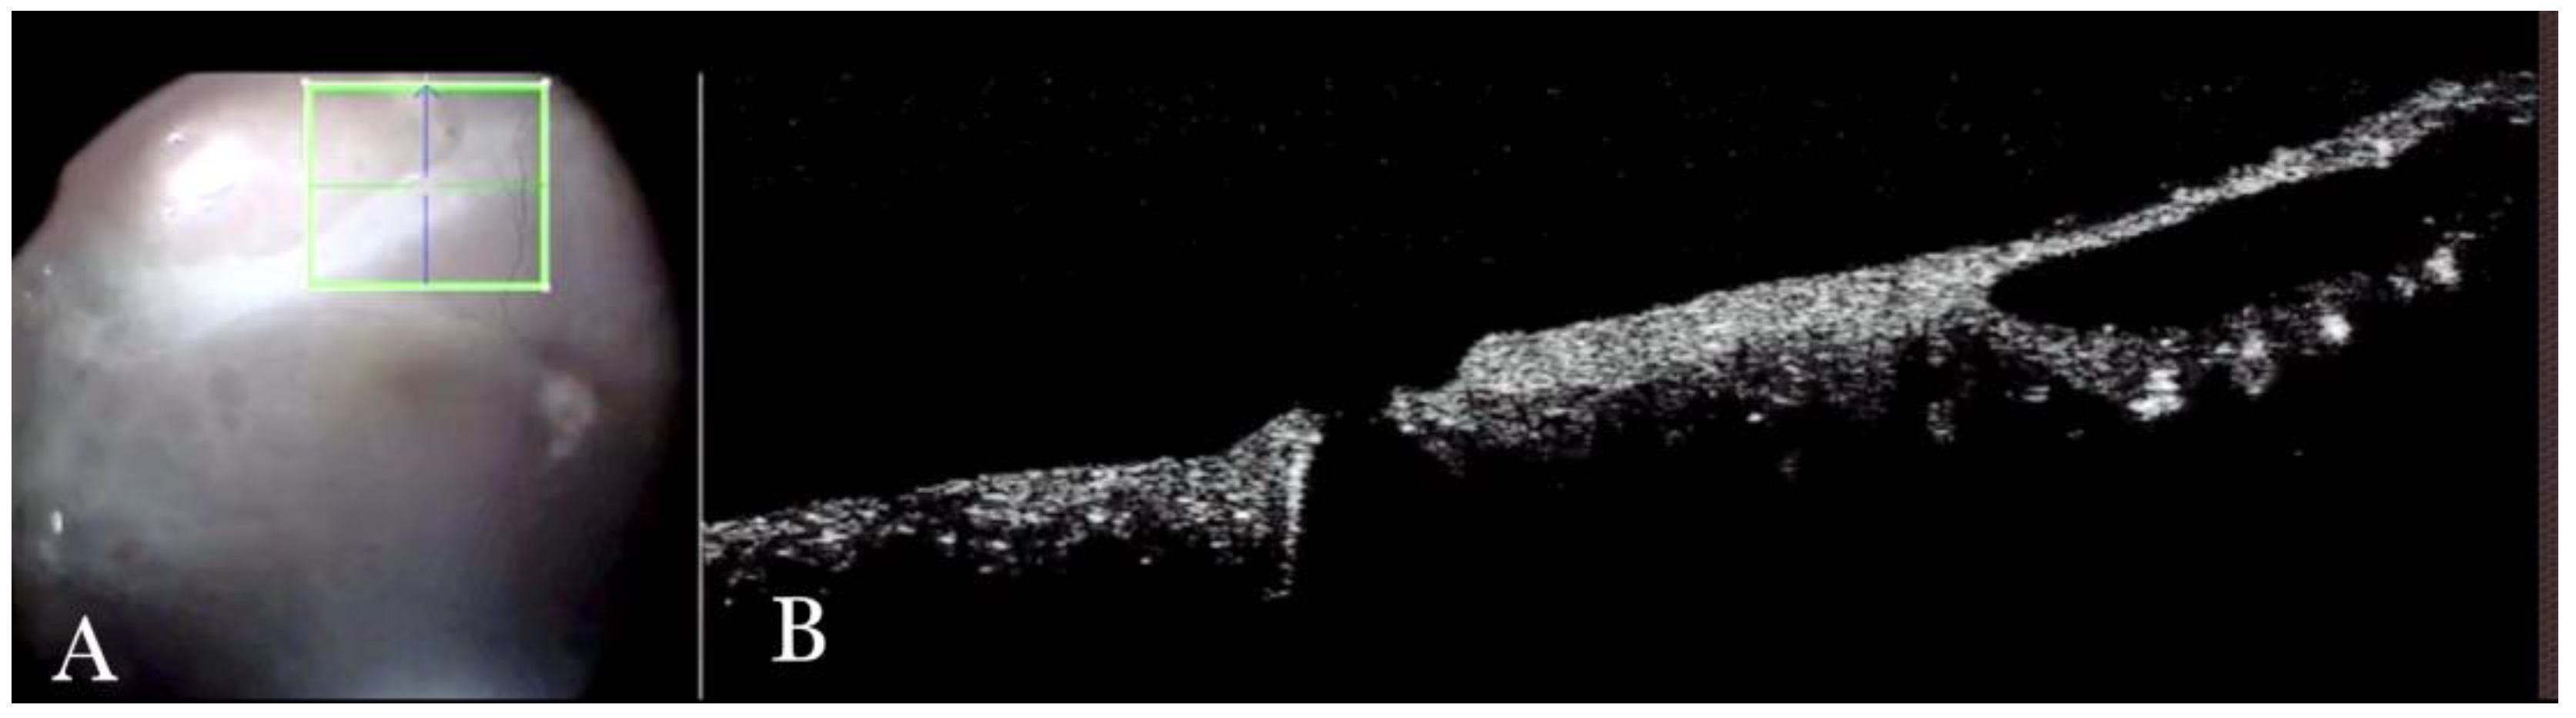

3.2. Primary and Recurrent Macular Holes

Forty (15.09%) eyes diagnosed with either primary or recurrent macular holes (MHs) were treated. In primary MHs, the i-OCT could confirm the correct positioning of the ILM flap on the hole (Figure 2) in simple cases and in more difficult cases. A complex case of persistent macular hole is presented in Figure 6 and Supplementary Video S5, which shows hole closure by autologous retina transplant (ART).

Figure 6.

(A) Microscope view showing the macular area after autologous choroidal transplant. A full-thickness patch of the choroid has been transplanted from the peripheral area under the macula. A macular hole occurred. (The green box indicates the field-of-view of the OCT scan, the green and blue lines within the green box show the vertical and horizontal scan planes). (B) The intraoperative optical coherence tomography (i-OCT) B horizontal (green arrow) scan shows the retina attached over the choroidal patch. An autologous patch of the retina (white arrowhead) was transplanted into a macular hole. (C) The i-OCT B vertical (blue arrow) scan shows the retina attached over the choroidal patch. An autologous patch of the retina (white arrowhead) was transplanted into a macular hole.